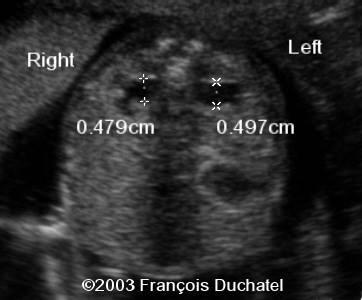

When should the kidneys and the bladder be seen?

15 weeks

What do normal ureters measure?

1 mm

Pyelectasis

What is pyelectasis?

abnormal collection of urine within the renal pelvis 5-9 mm

Caliectasis

Caliectasis

What is calyectasis?

rounded calyces with renal pelvis dilatation